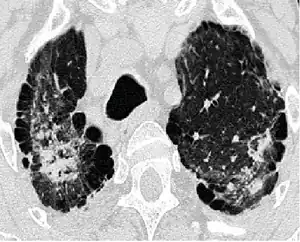

| HRCT-scan of severe aluminosis (with subpleural bullae) | |

Findings may vary, showing nodular or slightly irregular opacities that may merge into more prominent forms, most frequently in the upper lung fields, sometimes in the lower lung fields, and less frequently a diffuse micro nodular pattern. In severe cases, pulmonary fibrosis with honeycombing was described.[4]